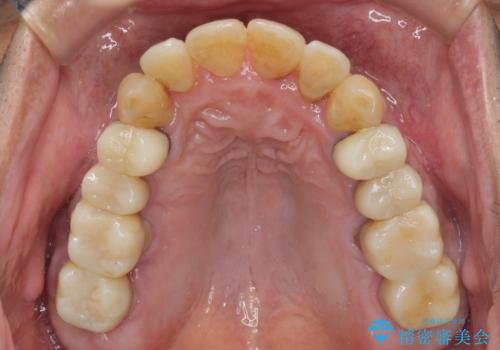

歯列不正と歯周病 総合歯科治療による全顎治療

- 前歯がのデコボコや、奥歯に咬んだときに痛みがあるとのことで来院された患者様です。

全体的に問題が多く、全てをしっかりと治療したいとのことでした。

全体的に中等度の歯周病と診断されたため、歯周外科処置やインプラントによる咬合回復から進めて行き、矯正治療による歯列改善を行った後にオールセラミッククラウンにて補綴することとしました。